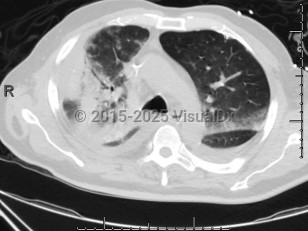

Chlamydophila pneumoniae pneumonia

Chlamydophilia pneumoniae (also known as Chlamydia pneumoniae) is an obligate intracellular bacterium that causes pneumonia.

Clinically, it is not possible to distinguish pneumonia due to C. pneumoniae from pneumonia due to other respiratory pathogens. Also, it is possible to be infected by more than one pathogen at the same time (eg, with Streptococcus pneumoniae and C. pneumoniae). In these cases, it is difficult to determine if C. pneumoniae is responsible for the patient's symptoms or if the other pathogen is more important.